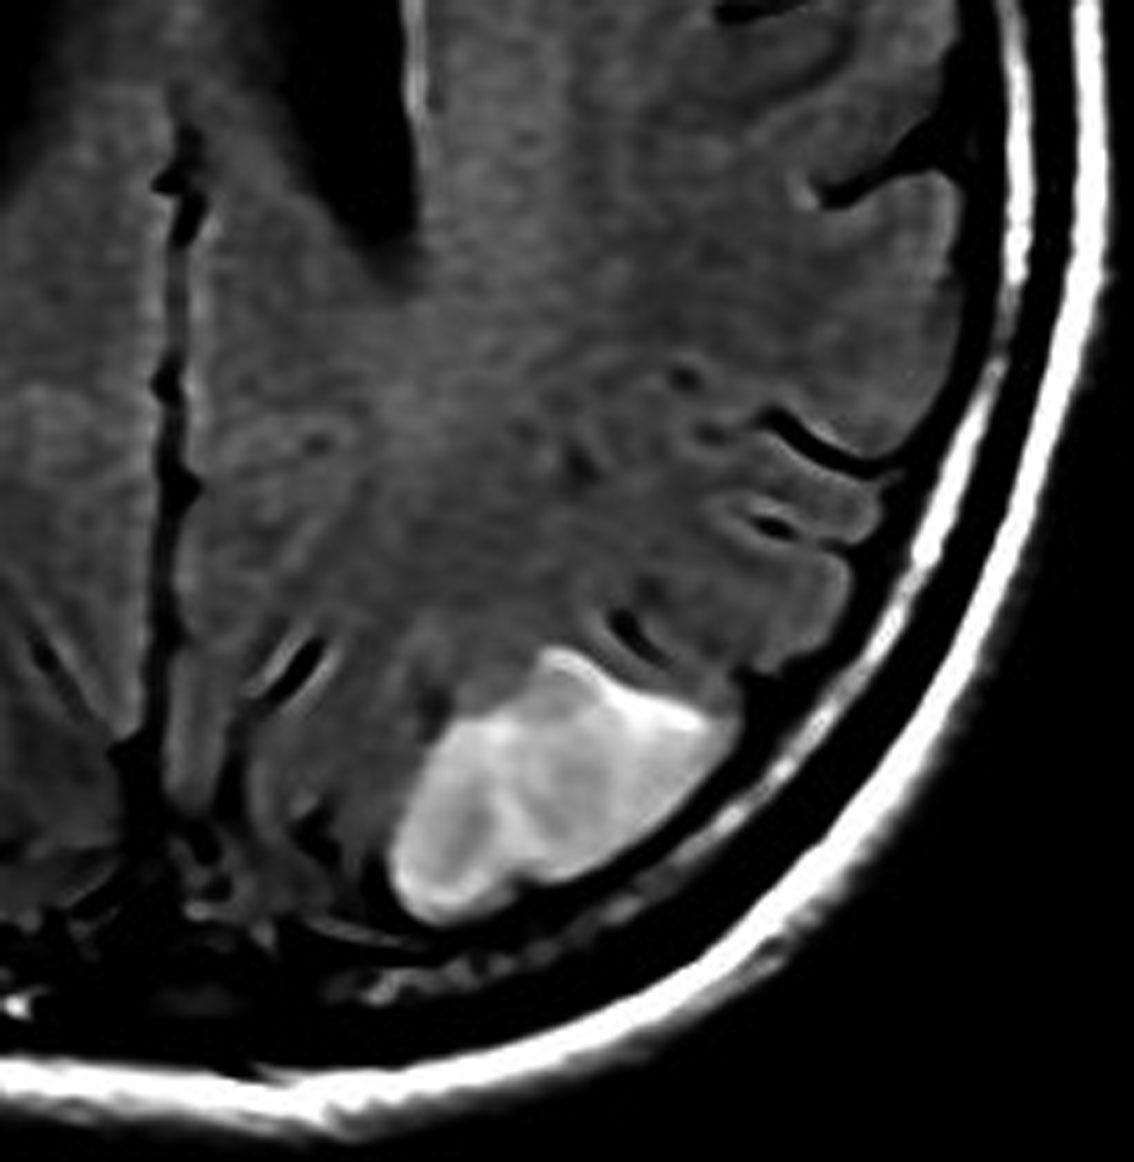

左側頭葉のびまん性星細胞腫です。左側のT1強調ガドリニウム像ではほとんど腫瘍は見えません。真ん中のT2強調画像でも見づらいです。右側のフレア画像で白くにじんでいるところに腫瘍があります。どこまでが腫瘍の境界なのかがはっきりしない腫瘍です。左の海馬(記憶の中枢)を侵し,とてもゆっくり大きくなるタイプで,この患者さんは10年以上治療をしないで経過を見ています。全摘出できない星細胞腫グレード2です。

フレア画像です。左上前頭回の星細胞腫ですが,境界がとてもはっきりしていて限局性 localized single gyrus glioma です。びまん性 diffuseには見えません。IDH1の変異があり,1p/19qの欠失はないので星細胞腫グレード2です。上の例とは全く違う臨床像を示しますが,分子病理でも区別はつきません。頑張って早めに全摘出して治してしまった方がいいタイプです。再発を避けるために,supratotal resectionと言って,周囲の正常脳組織も10mmくらい余分に摘出します。